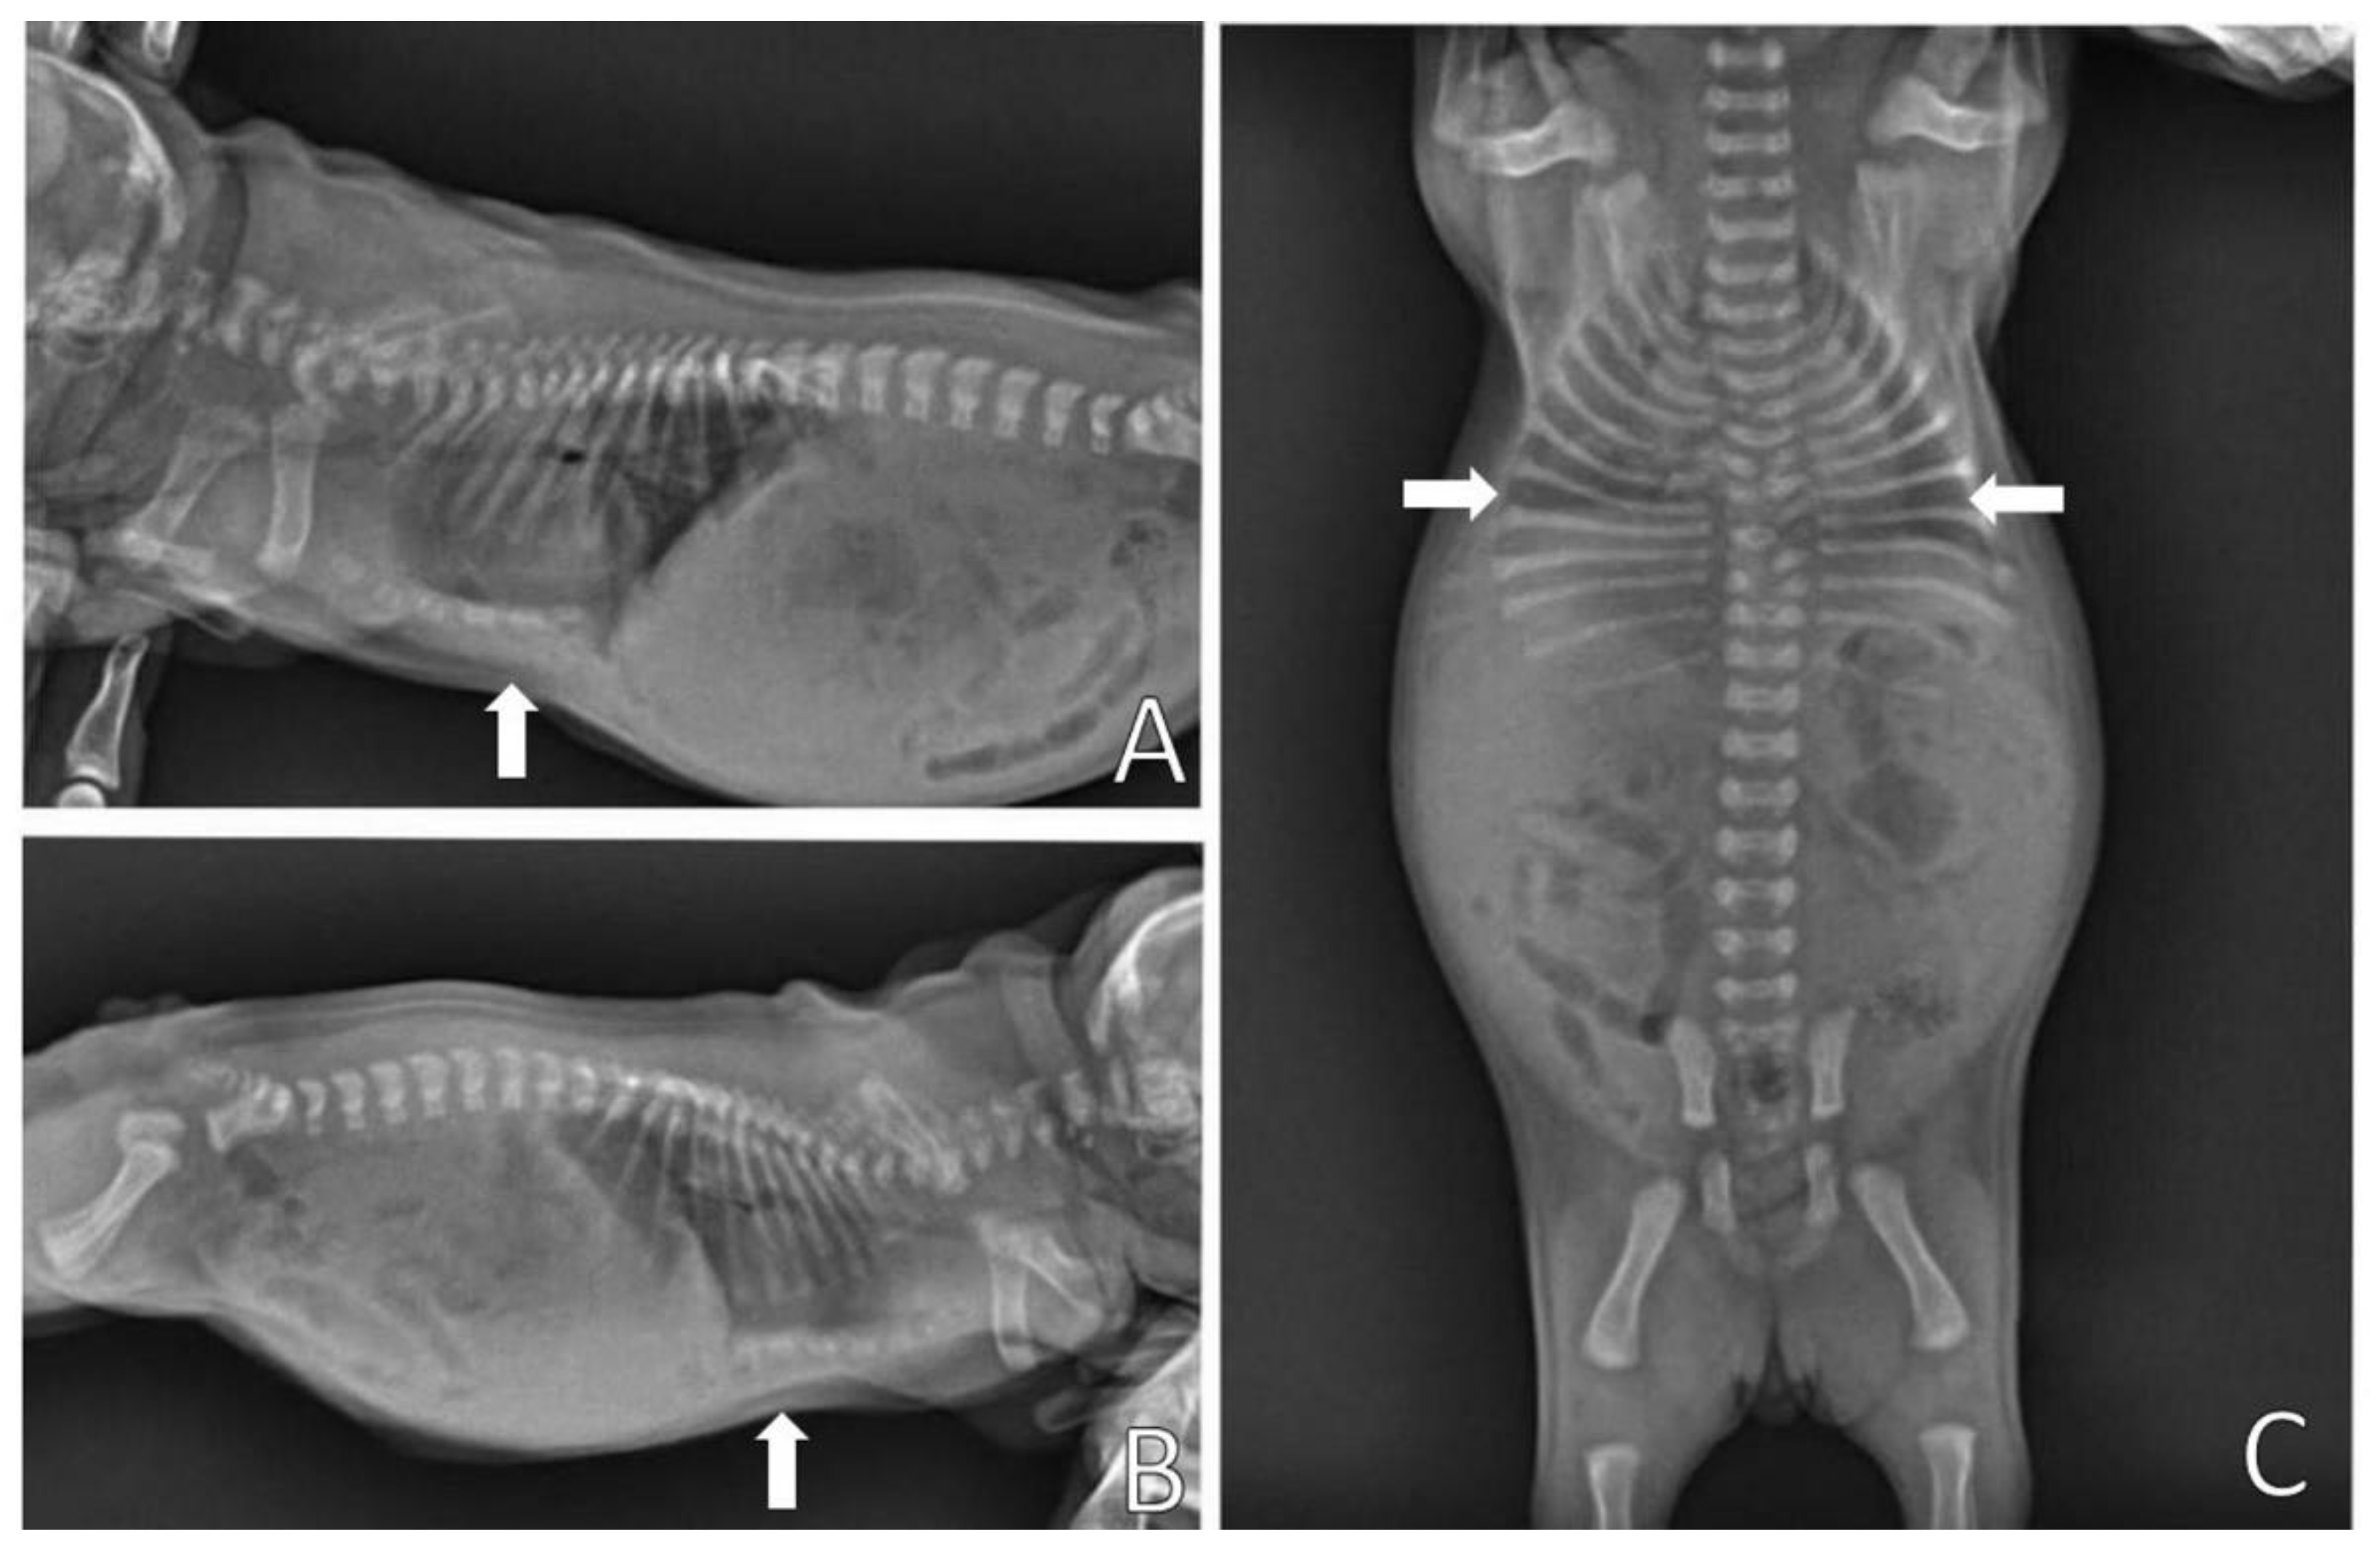

On the chest X-ray (Figure 3), it was possible to observe the ventrodorsal deviation of the sternum in the medial and caudal region of the ventral thorax, diagnosing pectus excavatum. The frontosaginal and vertebral index corresponded to 1.8 cm (≤2.0 cm) and 10.2 cm (>9 cm), respectively, classifying the pectus as mild grade. In addition, cardiopulmonary alterations were found: pneumonia with alveolar pulmonary pattern, pulmonary hyperinflation, rounded cardiac silhouette (globose aspect) and cardiac deviation to the left.

Figure 3.

Chest X-ray. (A) Right side position and (B) left side position, demonstrating ventrodorsal deviation of the sternum bone (arrows); (C) Ventrodorsal position demonstrating narrowing of the thorax (arrows), pneumonia and left cardiac deviation.

Figure 4 shows the chest X-ray of a neonate of the same litter, without thoracic alterations, to compare chest structures and aid in diagnosis.

Figure 4.

Normal thoracic radiographic examination. (A) Right side position; (B) Left side position; (C) Ventrodorsal position.